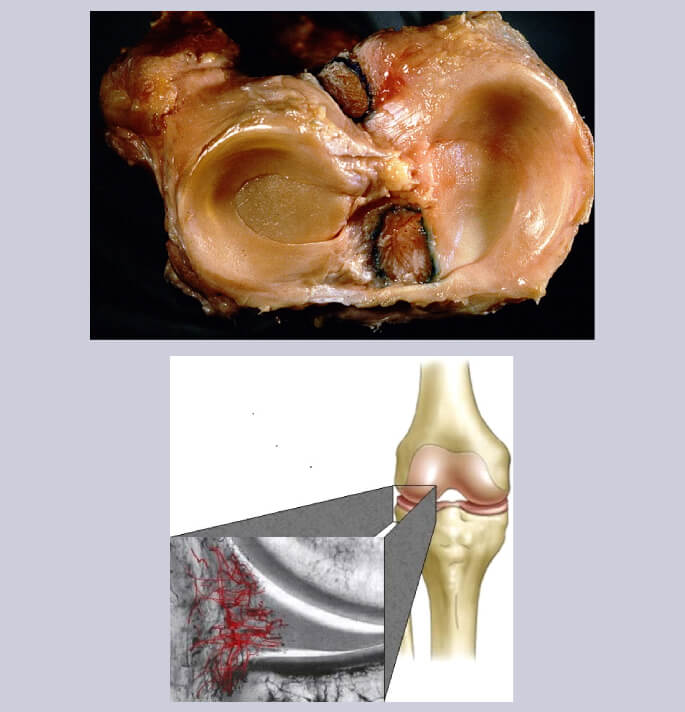

Tussen het onderbeen en het bovenbeen liggen zowel aan de binnen- en als aan de buitenzijde een elastische schokbreker (meniscus) bestaande uit fibrocartilago)

De belangrijkste functie van de meniscus bestaat in het optimaal aanpassen van het gewrichtsoppervlak tussen het wat rondere bovenbeen en het vlakkere onderbeen gewrichtsgedeelte.

Daarnaast speelt de meniscus ook een secundaire rol in de stabiliteit van de knie

Gezien de functie van de meniscus (optimalisatie van de gewichtsverdeling tussen het boven en het onderbeen) is het impact van deze letsels ( zeker bij jonge patiënten) niet te onderschatten daar deze letsels kunnen leiden tot vervroegde slijtage van het kraakbeen (artrose)